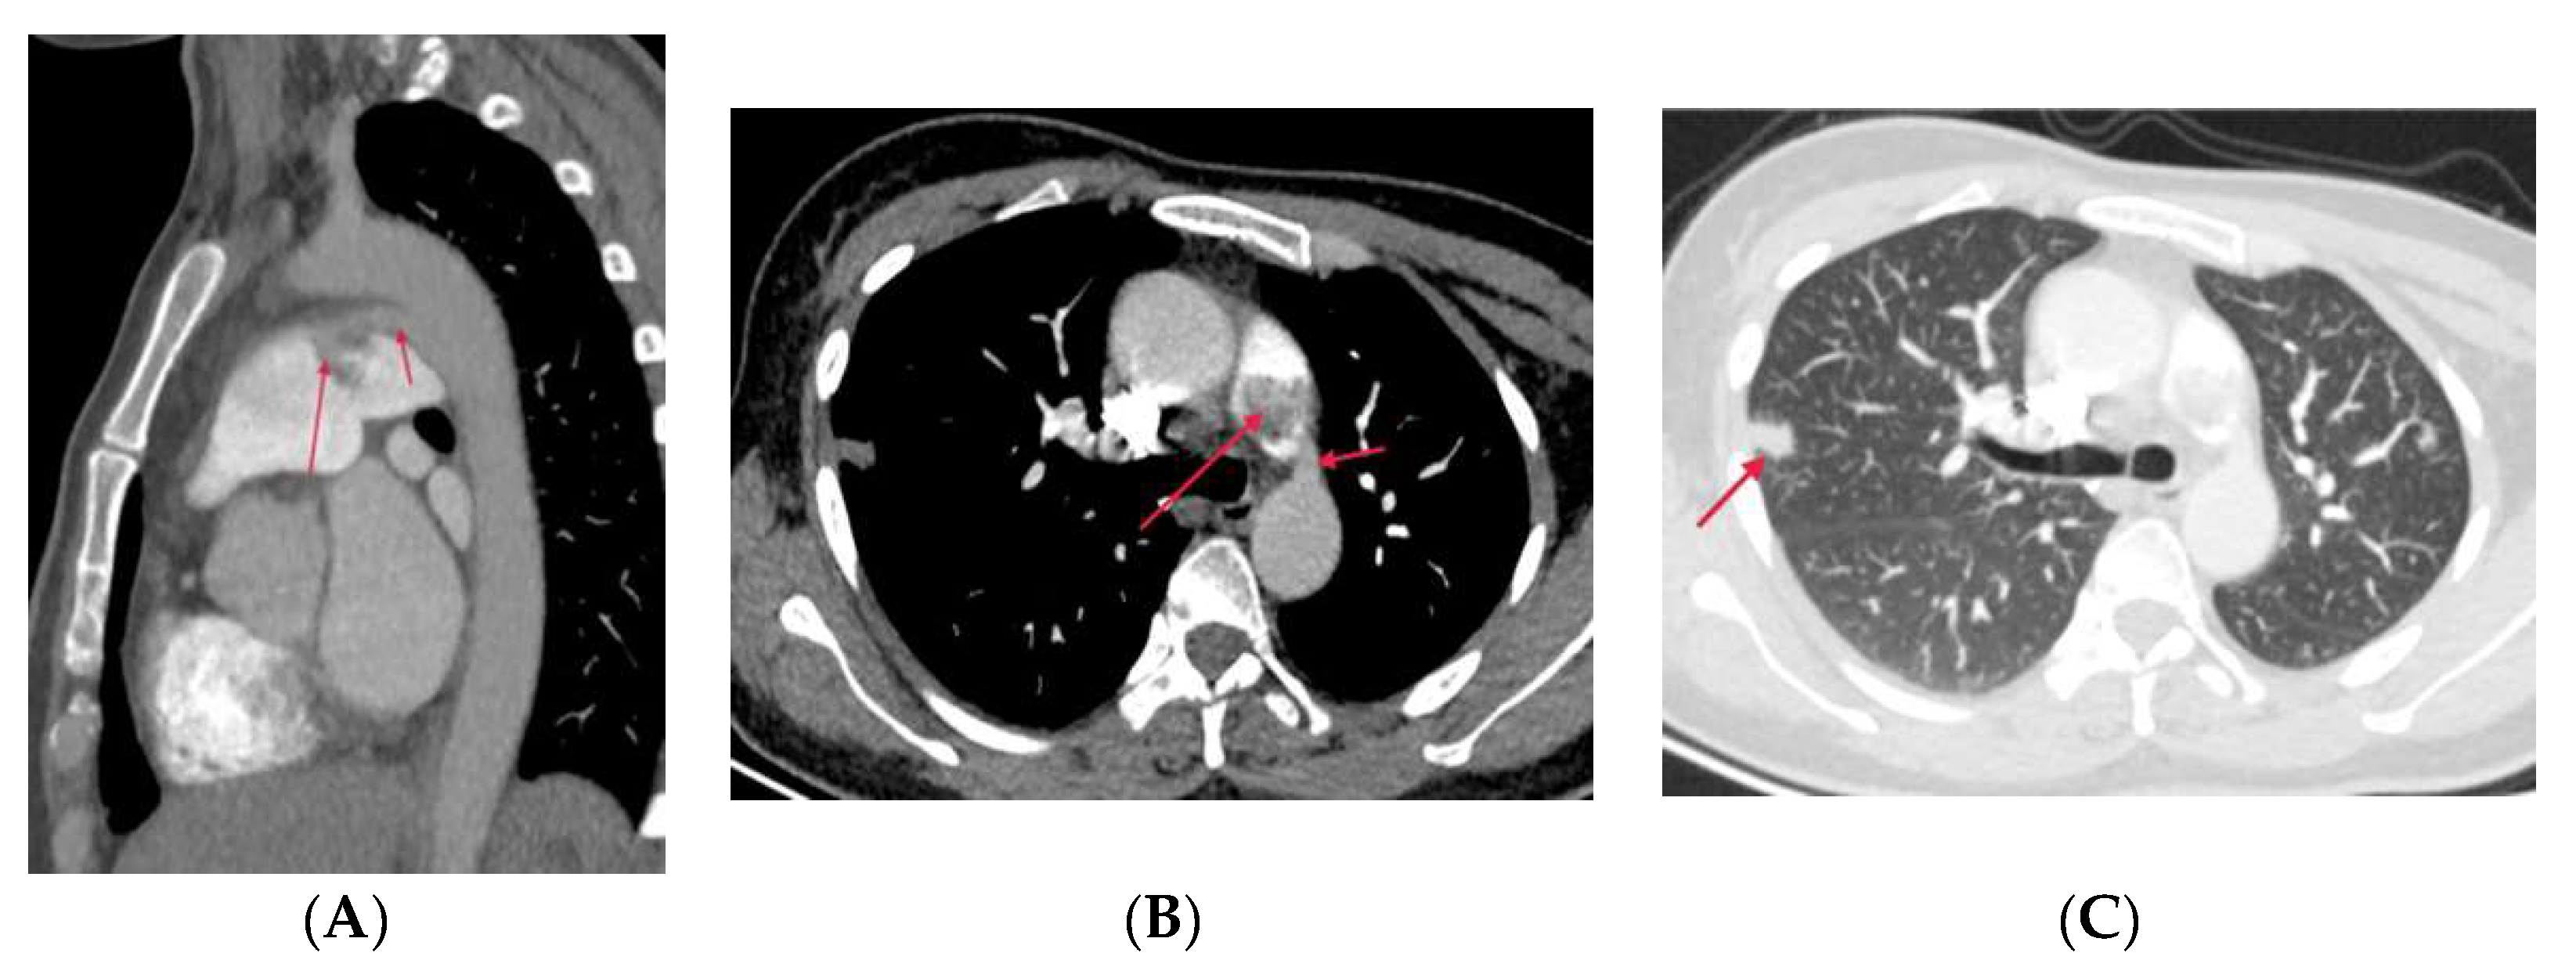

4. Complications of Radiofrequency Ablation Of Atrial Fibrillation

5. Conclusions